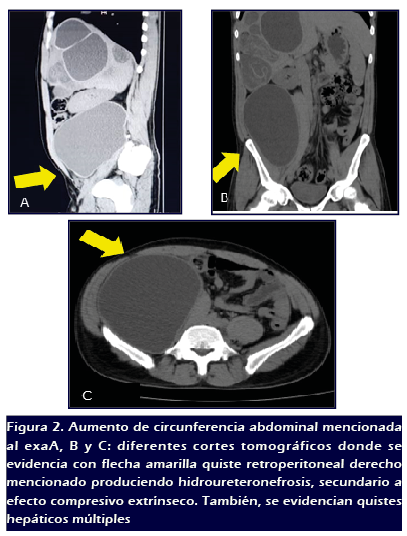

En TAC abdominopélvica (doble contraste) se evidencia

parénquima hepático aumentado de volumen a predominio de

lóbulo derecho con múltiples lesiones quísticas,

la mayor de 10 x 10cm de contenido heterogéneo, en el

músculo psoas ilíaco derecho se aprecia imagen hipodensa

quística de paredes gruesas, de aproximadamente 20 x 17cm, la

cual ocasiona efecto de masa sobre estructuras de hemiabdomen derecho

desplazándolas hacia la región central. Se hallan

lesiones de quistes a nivel retroperitoneal derecho de 15 x 17cm de

contenido homogéneo de bordes regulares bien definidos en

íntima relación en columna vertebral lumbar y vena cava

inferior, además de lesiones quísticas múltiples

en bazo de 2x 2cm. (

Figura 2).